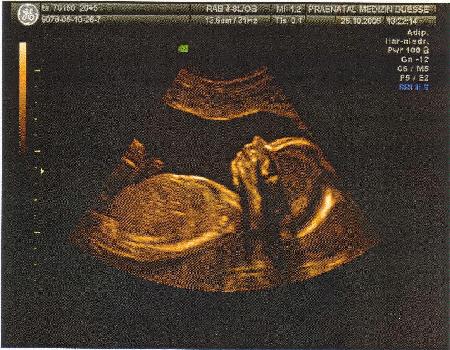

21.Woche